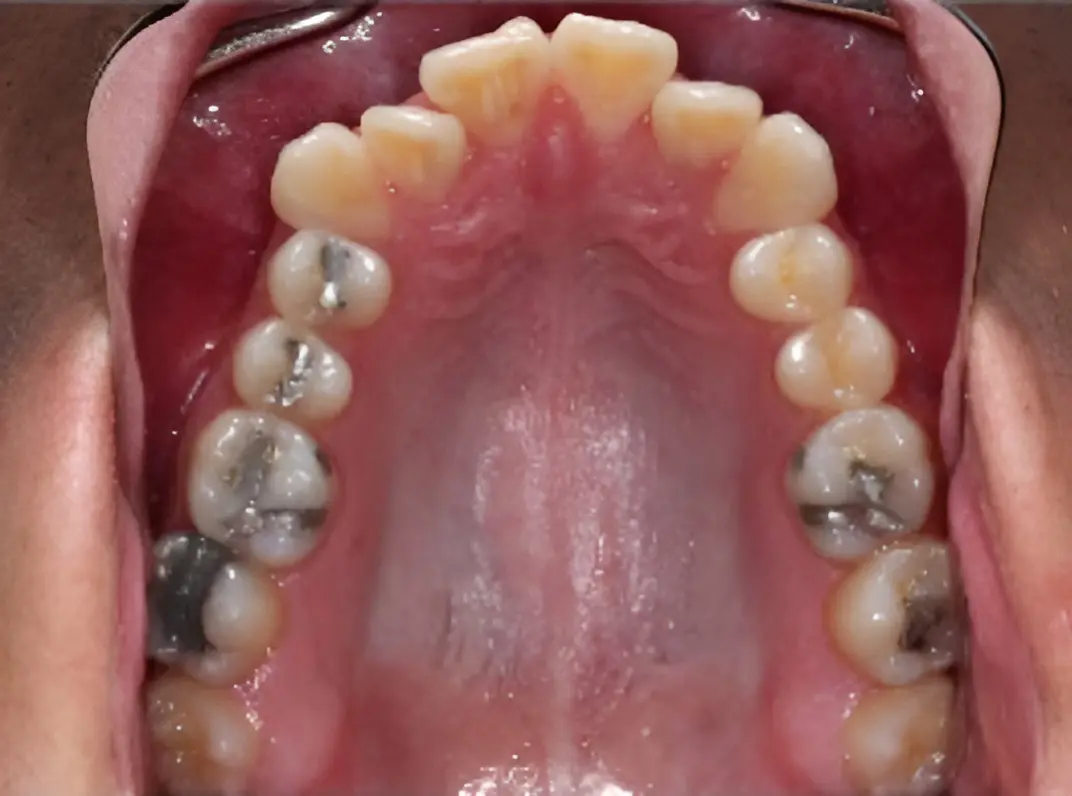

Before

After